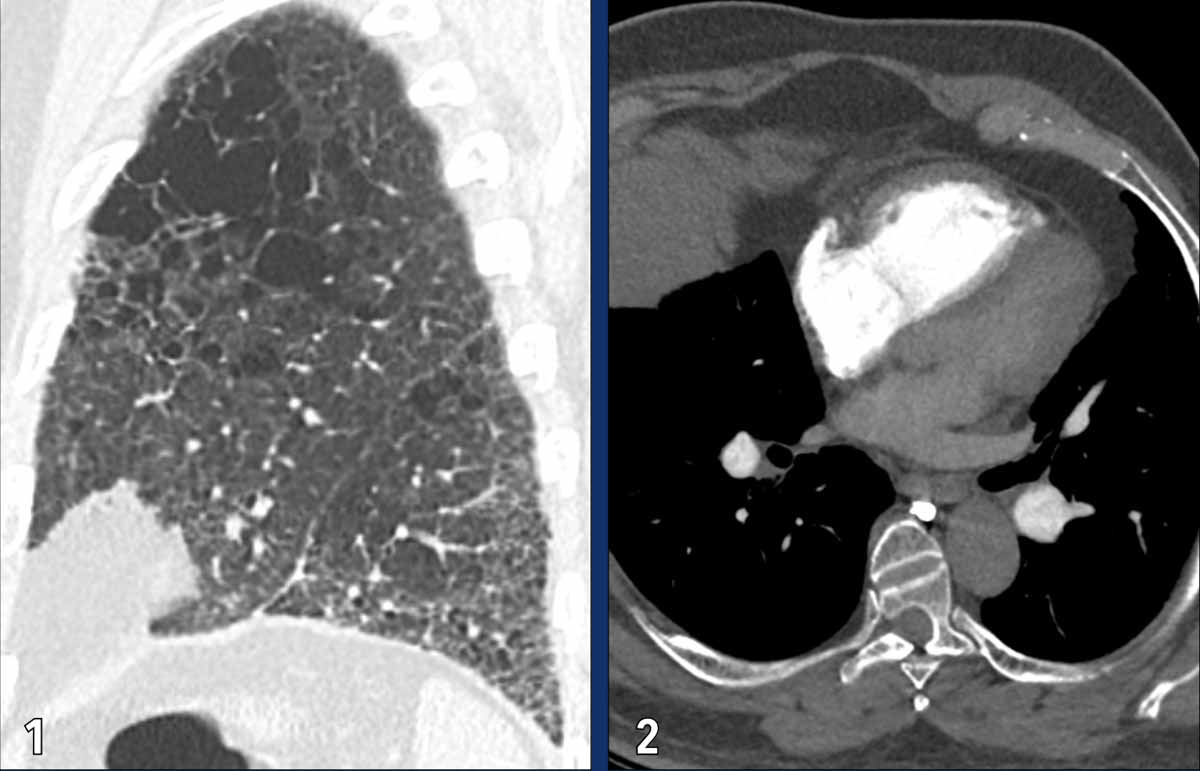

PVOD

Pulmonary veno-occlusive disease (PVOD) is a rare subtype of PAH.

It is caused by narrowing and obliteration of the small pulmonary veins (venules), as opposed to other causes of group 1 pulmonary hypertension in which the pre-capillary arteries are primarily involved.

The venous occlusion leads to post-capillary pressure build-up and subsequently pulmonary arterial hypertension.

The classic CT triad in PVOD includes:

1. Smooth interlobular septal thickening.

2. Centrilobular ground-glass opacities.

3. Enlarged mediastinal and hilar lymph nodes resulting from chronic lymphatic congestion.

PH due to left heart disease

Pulmonary hypertension due to left heart disease  is asseigned to WHO group 2.

It occurs when the left heart is unable to effectively accommodate or eject the blood returning from the lungs.

This results in a backward transmission of pressure into the pulmonary circulation, first leading to elevated pulmonary venous pressure and subsequently also elevated arterial pressure.

It may result from:

• Systolic dysfunction (i.e., impaired left ventricular contraction)

• Diastolic dysfunction (i.e., reduced ventricular filling due to myocardial or pericardial stiffness)

• Severe valvular disease, particularly mitral or aortic valve pathology.

Given the high prevalence of cardiac disease, this is the most common form of pulmonary hypertension.

Images

In this patient with left heart disease the findings are:

1. Dilatation of the main pulmonary artery.

2. Dilatation of the right atrium and mild thickening of the myocardium of the right ventricle.

3. Dilatation of the left atrium

4. Pleural fluid (white arrow).

5. Smooth interlobular thickening (black arrow).